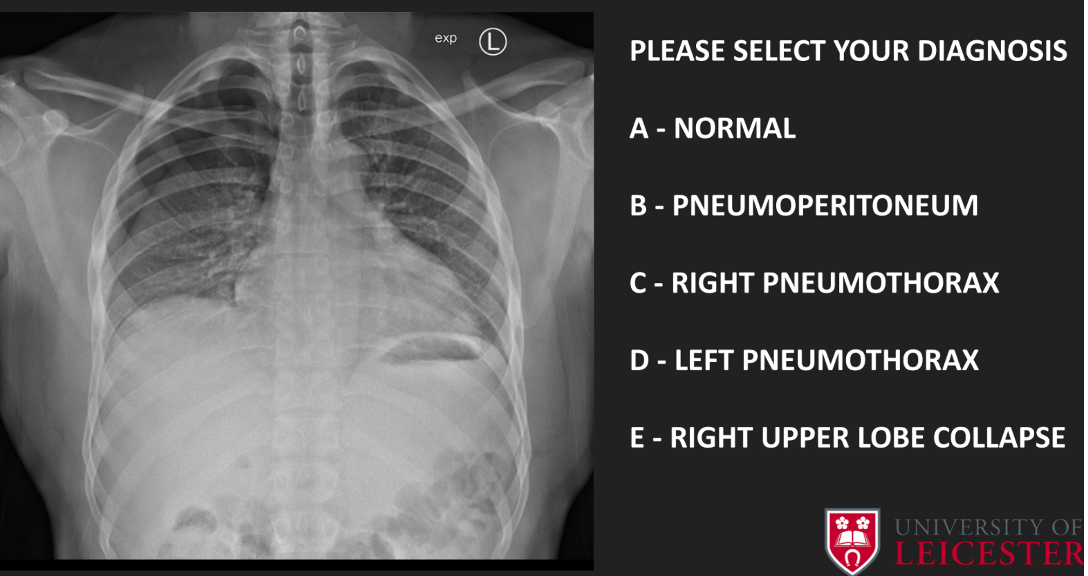

Q

A

C- right pneumothorax

21

diagnosed

C- right upper lobe collapse

• Atelectasis- mediastinum pulled towards collapse